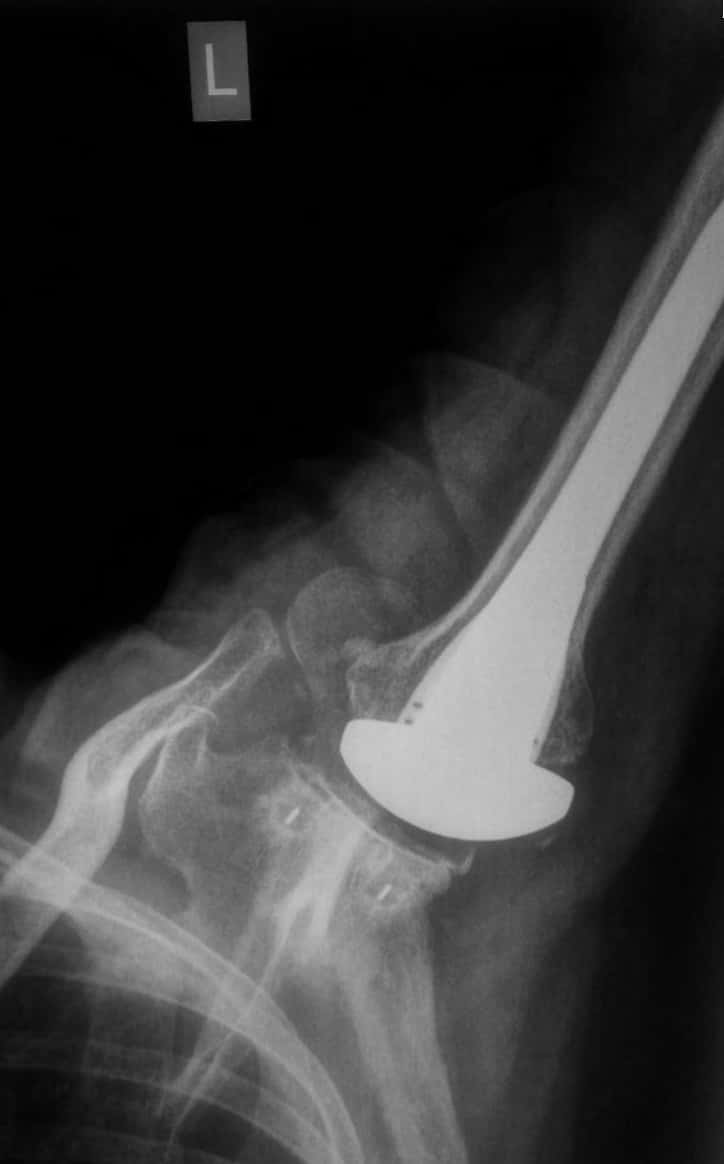

A Typical X-Ray of a well functioning Shoulder Replacement

Complete wear or loss of normal smooth cartilage over the humeral head (Ball), Damaged cartilage over glenoid (socket), Replaced socket, replaced ballthis is how the replaced shoulder typically looks on an x ray!!